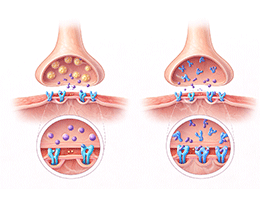

다발경화증 (Multiple sclerosis)

길랭바레증후군 (Guillain–Barré syndrome)

중증근무력증 (Myasthenia gravis)

신경병증성통증 (Neuropathic pain)